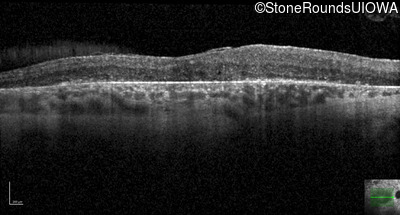

Optical Coherence Tomography - Right - 20/25 -1

Exemplar / OCT Stack

OCT Stack